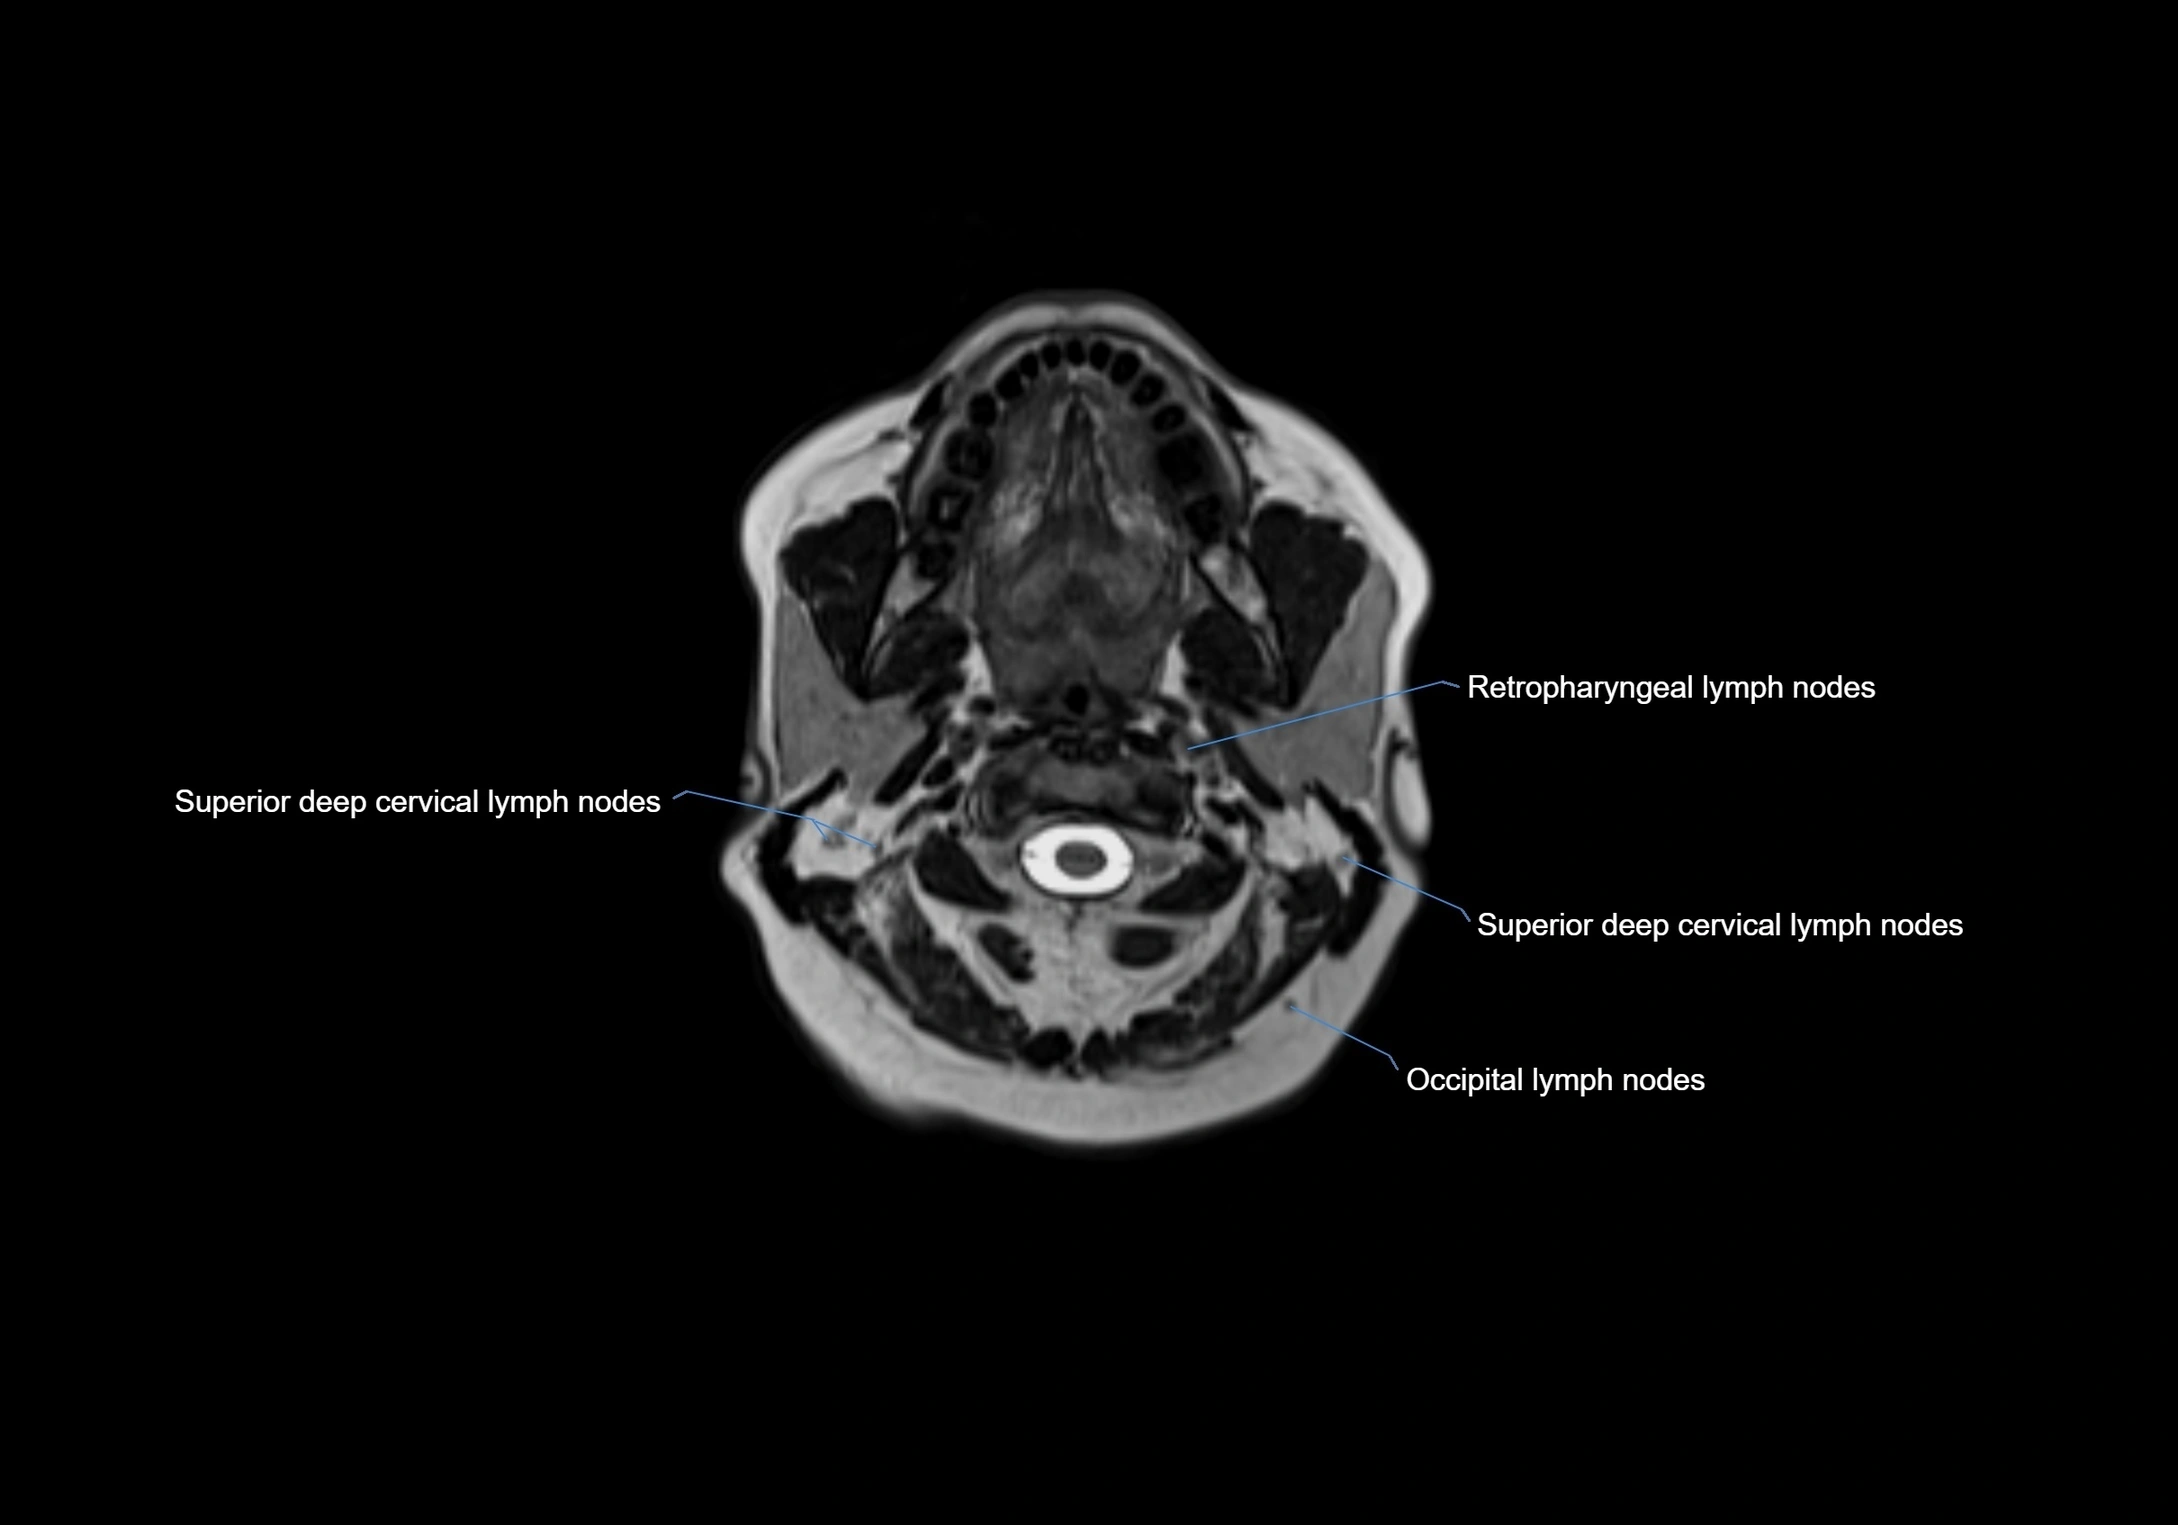

Accessory lymph nodes are small, secondary lymph nodes located along the main facial and cervical lymphatic chains, often adjacent to primary lymph nodes, such as preauricular, submandibular, or occipital nodes. They are typically less than 5 mm in diameter, embedded within subcutaneous fat or connective tissue, and may be variable in number and location. These nodes provide additional filtration and immune surveillance for lymph collected from the face, scalp, and neck regions. Accessory lymph nodes are usually non-palpable in healthy individuals but may enlarge in response to infection, inflammation, or metastasis, making them clinically significant.

Location

• Found along primary lymph node chains, including preauricular, submandibular, parotid, and occipital regions

• Embedded in subcutaneous fat or superficial fascia, often lateral or posterior to primary nodes

• Variable in number; may occur unilaterally or bilaterally, depending on individual anatomy

MRI images